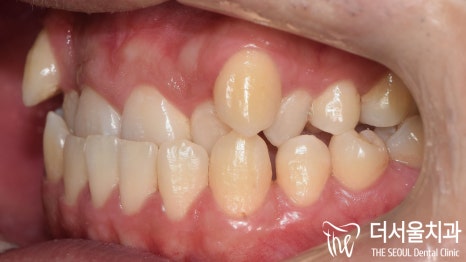

『2년 반의 모든 과정이 끝이 났습니다!』

너무 오래 걸린게 아닌가? 생각이 들 수 있는데요.

class 3은 유독 다시 틀어지는 일이 많습니다.

성남치과에서는 틀어지는 것을 방지하기 위해

일부로 천천히 마무리를 도와드렸죠.

너무 빠르게 끝나게 되면

원래 상태로 되돌아가는 회귀,

relapse가 빨리 생기기 때문에

일부로 이동을 천천히 유도한 것도 있습니다^^

주걱턱 비수술 치아교정 과 충치치료,

임플란트 식립까지 마무리 되었는데요.

문제가 되었던 위,아래 앞니는 물론이며

덧니 그리고 배열까지,

흠 잡을 곳 하나 없이

좋은 결과를 얻을 수 있었습니다.

치료기간: 2021.01.16~2023.06.29